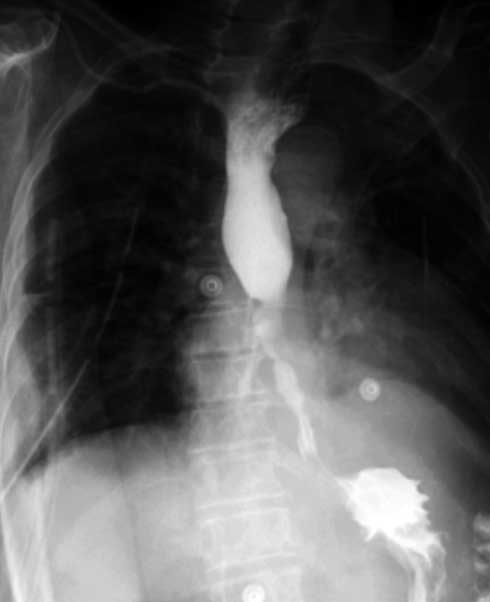

Mujer de 64 años, con antecedente de mastectomía radical izquierda por carcinoma de mama no especificado en el año 2000, recibió quimioterapia, radioterapia neoadyuvante y tamoxifeno por 5 años. Posterior a su alta hospitalaria, la paciente permaneció sin vigilancia. En el año 2014 la paciente inició con disfagia a sólidos y líquidos, dos años después por panendoscopía se documentó la presencia de estenosis de 80% de la luz esofágica. Se realizaron tres dilataciones endoscópicas, en la última con perforación incidental confirmada con esofagograma contrastado (figura 1).

Fuga del contraste del tercio medio-inferior de la pared lateral derecha y posterior del esófago con relación a perforación.